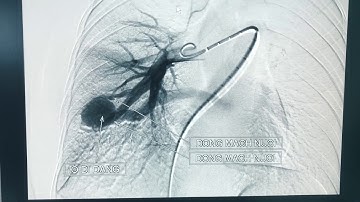

Dị dạng động tĩnh mạch thận– những điểm mới trong Chẩn đoán hình ảnh và can thiệp điện quang